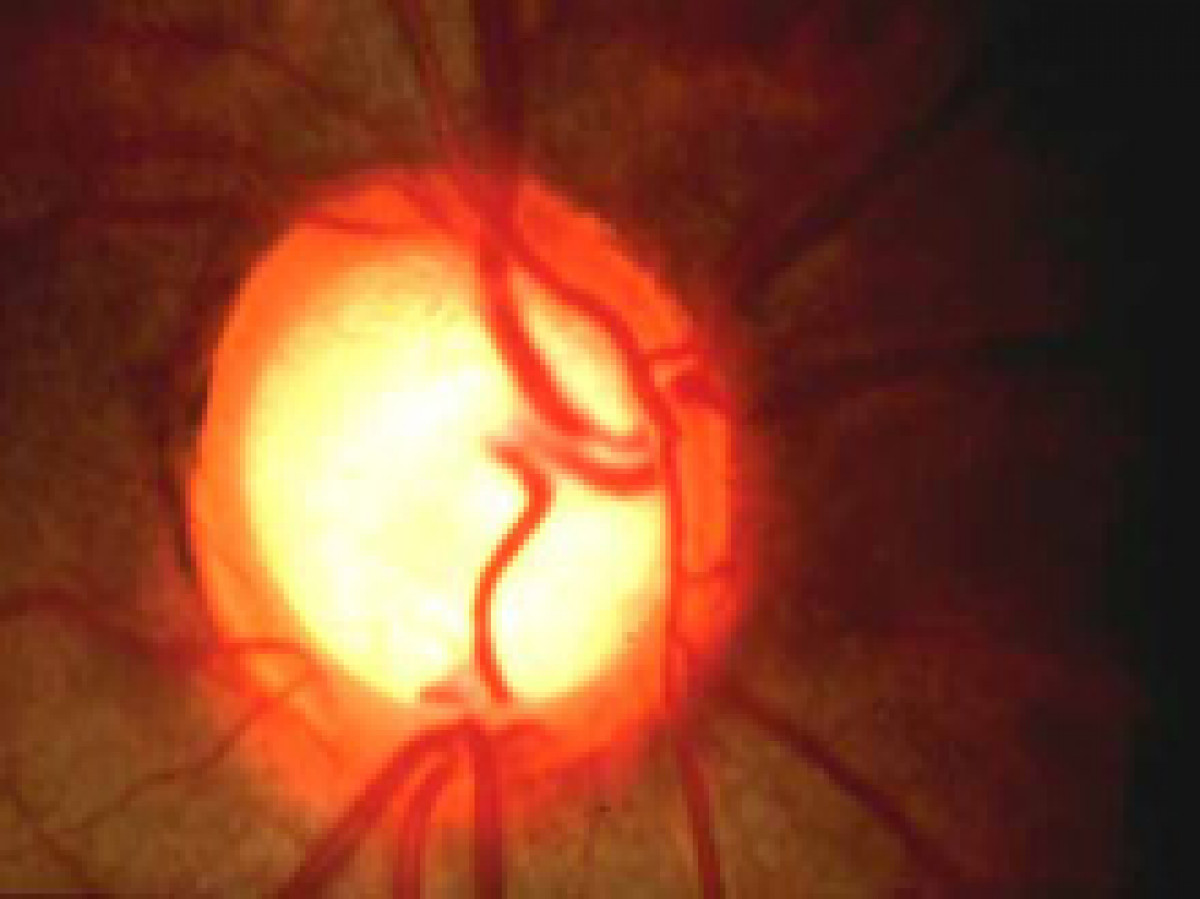

En fases tempranas de esta enfermedad, que afecta al nervio óptico, por acumulación de fluido en la parte anterior que aumenta la presión intraocular y puede afectar a la visión e incluso llegar a la ceguera si no es tratado, el paciente puede "no experimentar síntomas y, en consecuencia, no es consciente de que padece la enfermedad", han explicado desde la entidad.